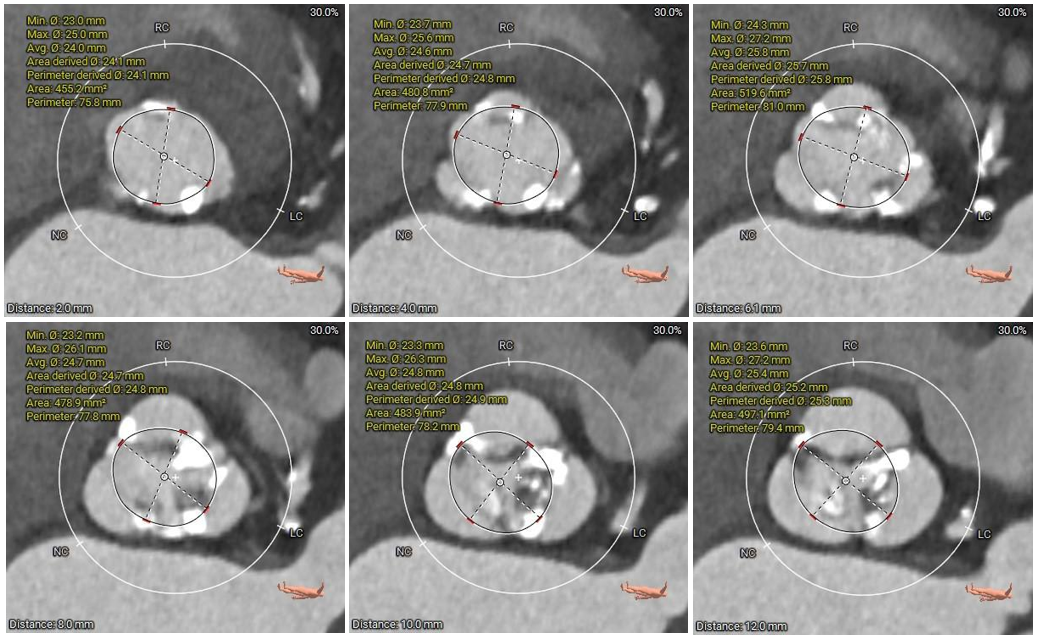

术前CT评估:

本例患者为主动脉瓣重度狭窄伴中度反流,因反复严重心衰伴心绞痛多次住院,同时合并高血压病、陈旧性脑梗死等基础疾病,一般状况不佳,无法耐受外科开胸手术,有强烈的微创换瓣手术意愿;患者术前心脏彩超、CT等评估适宜行TAVR手术,TAVR手术指征明确。CT分析提示患者为Type1型二叶式主动脉瓣,瓣叶明显增厚伴重度钙化,左右窦间可见钙化融合嵴,瓣膜植入后受钙化嵴挤压影响存在瓣周漏风险;此外,患者左窦间存在长条状钙化延伸至瓣环下10mm水平,瓣膜植入后可能压迫传导束,存在起搏器植入风险,对瓣膜释放位置及精准度要求较高,需要术者快速、精准的操作能力及手术团队的密切配合。

手术过程中,在完成跨瓣操作后,23mm球囊预扩有轻微腰征、无造影剂渗漏,预装TaurusElite AV29瓣膜到位,输送系统快速、顺利地完成过弓、跨瓣操作,于瓣环上约2mm定位释放;针对本例患者瓣叶明显增厚伴重度钙化,左右窦间可见钙化融合嵴的特点,TaurusElite瓣膜高密度流入端设计提供了足够的径向支撑力,保证了瓣膜的锚定力,瓣膜内外双裙边设计能提供良好的辅助锚定力,有效减少瓣周漏。此外,本例患者左窦间存在长条状钙化延伸至瓣环下10mm水平,释放位置偏深可能存在起搏器植入风险,TaurusElite瓣膜具有多次完全可回收,回收后可重新跨瓣、释放的特点,给予术者足够的信心完成高位释放的操作,释放后最终瓣架底端位于瓣环下约1mm,实现了释放位置的精准控制,有效的减少了起搏器植入风险,确保了手术安全、顺利的完成。这例手术为永州地区开展的第一台TAVR手术,填补了该地区TAVR技术空白,标志着永州市心脏瓣膜疾病诊治迈入了全新的微创治疗时代!